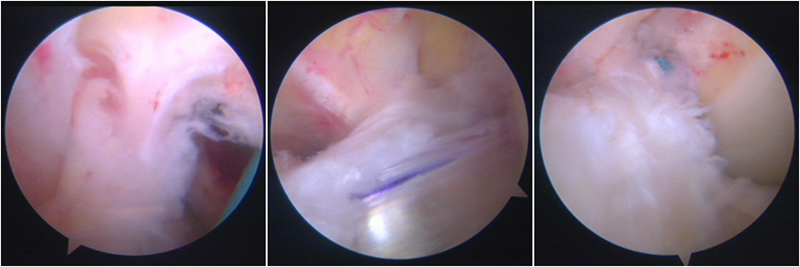

股骨侧保残骨道建立

股骨侧骨道建立,椭圆形扩孔保残9mm

韧带导入过程

送止血带后韧带表明血管膜